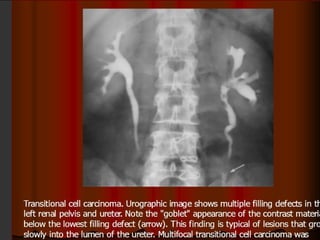

Ureteral filling defects may be single or multiple and

can usually be attributed to luminal, mural, or extrinsic

causes.

Urographic image shows

multiple filling defects in

the left renal pelvis and

ureter.

 Multifocal transitional

cell carcinoma was

confirmed in this case.